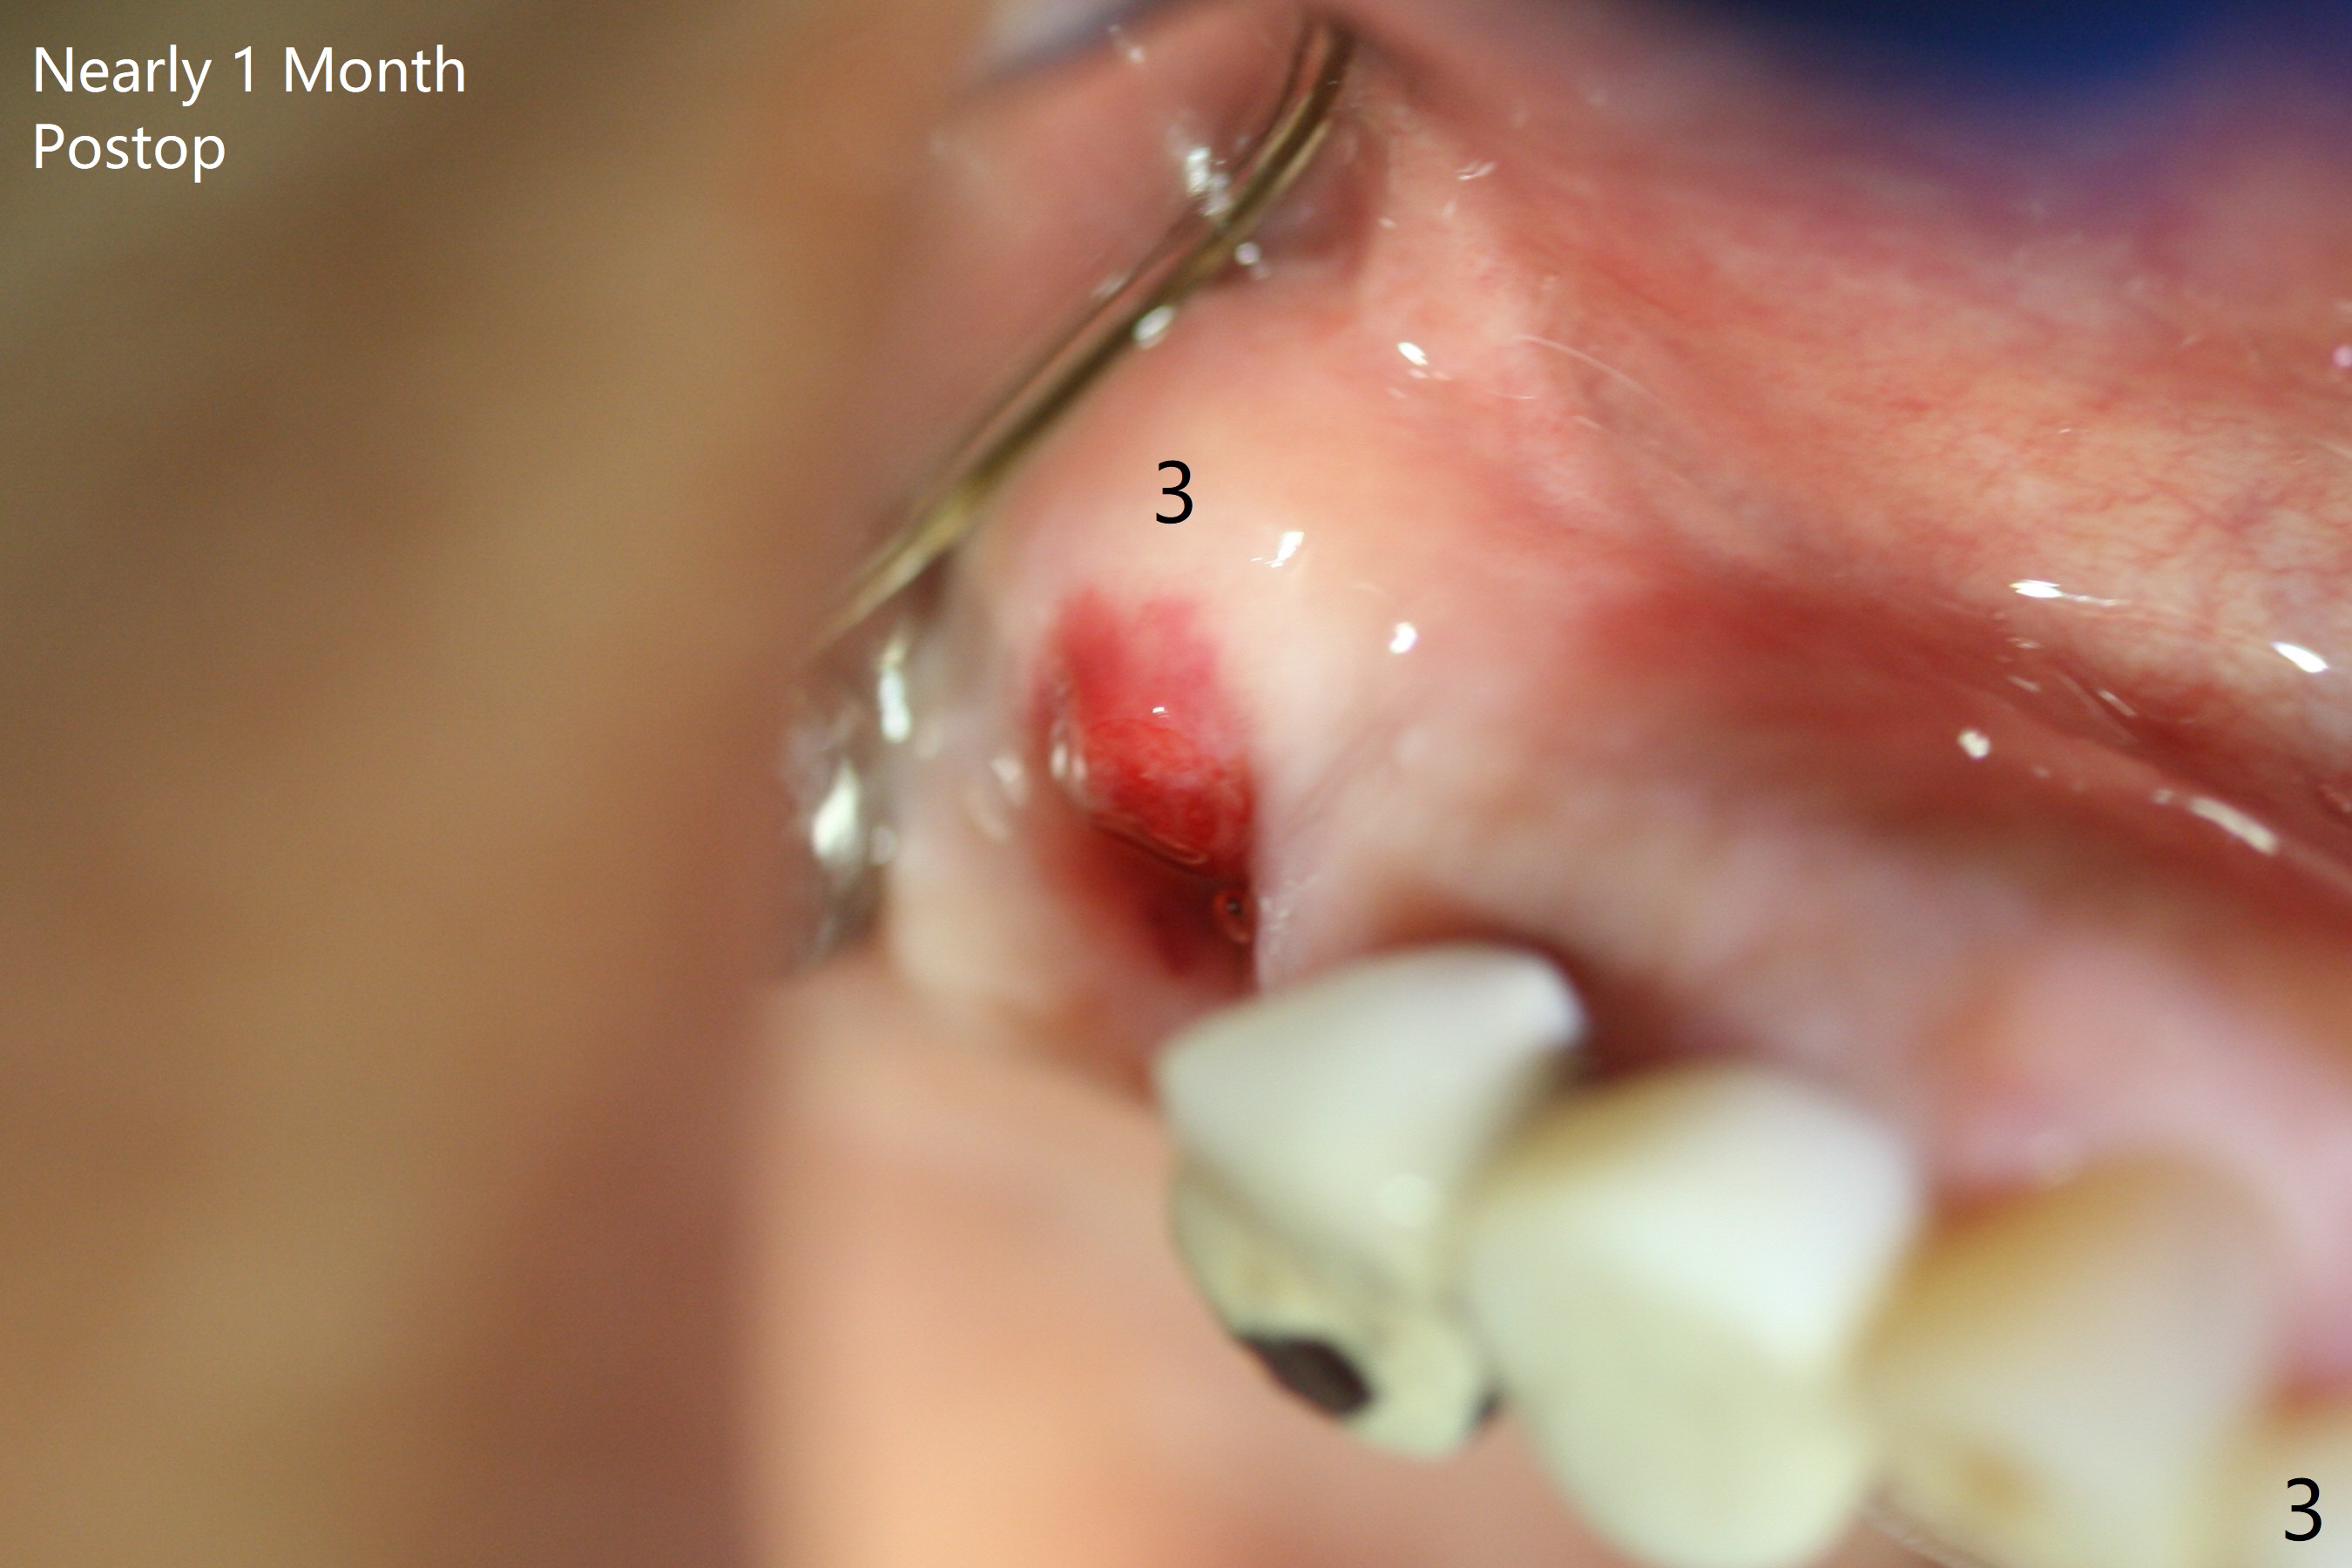

Osteotomy at the sites of #2 and 3 goes on as planned. Sinus lift using DIO 2.8 mm round bur with 6 and 7 mm stoppers (respectively) is carried on without certainty, because it is difficult to feel the stop through the osteotomy. The crest may be uneven or soft. It appears that the soft tissue landmark as a stop may be easier to identify. In fact a 3 mm IBS Magic Expander (an osteotome) was used for sinus lift at #3. The 2 implants are placed with 20 and 30 Ncm (Fig.1,2). Healing abutments are inserted. At 2-week follow-up, the patient reports "pain a few days earlier, took a pill of antibiotic, pain gone. UR metal is sharp". She does not take antibiotic regularly. Exam reveals that there is heavy plaque around #2,3 healing abutments. The buccal edge of #2 abutment is trimmed for comfort. Nearly 1 month postop, #3 healing abutment dislodges with buccal gingival erythema and edema with purulent discharge (Fig.3). Healing screw is placed at #3 with Amoxicillin and Chlorhexidine prescribed. One week later, the implant at #3 turns when the healing screw is retightened (Fig.4). After debridement, Vanilla graft is placed. There is no infection at #2 or 3 four months postop (Fig.5,6); the lingual gingiva is erythematous and edematous at #29 with mobility II (Fig.7 (vertical root fracture)). Uncover is conducted at the site of #3; there is no infection superficial 7.5 months postop (Fig.8). There is a large buccal defect upon incision with dark hemorrhage. In fact the bone density is low crestally (Fig.8 *). Bone graft is placed for the 2nd time. Eleven months later (1.5 years post implant placement), the bone regrows crestal (Fig.9 *). The crown at #3 is loose 1 year 5 months post cementation (Fig.10). After proximal trimming (Fig.11 *), the abutment at #3 is seated completely. After lab repair, crown oral cement, crown/abutment removal for excess cement removal, the crown/abutment cannot be torqued >25 Ncm (Fig.12, 30 Ncm). PA shows incomplete seating (Fig.12 <). Then the crown is sectioned so that the abutment has more freedom to be seated completely with pressure against the gingiva (the patient feels pain, Fig.13). Torque is 30 Ncm. After crown cementation, the abutment will not be removed for cement removal.